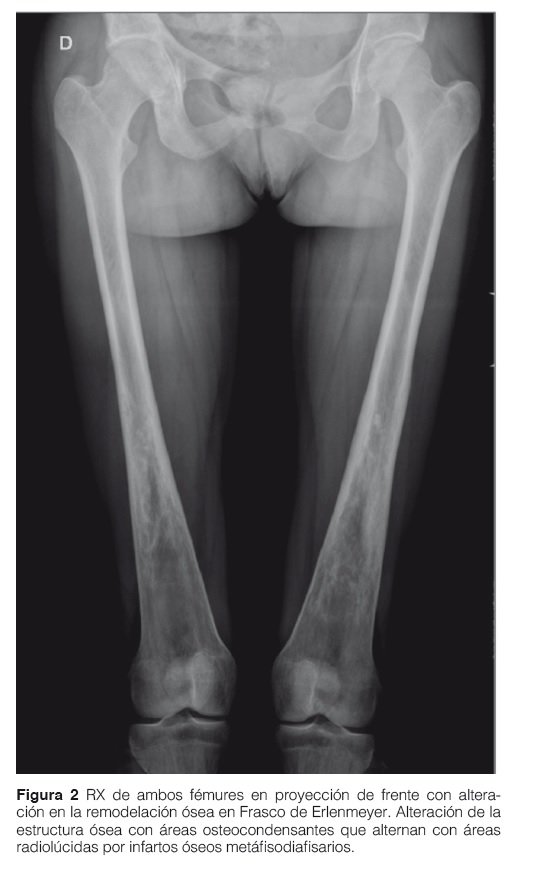

La Radiología muestra la forma y estructura del hueso además de sus relaciones articulares. Es un método simple, rápido y de fácil acceso. El hueso se afecta de manera secundaria a la afectación de la medula ósea. Por eso los cambios son tardíos. Sin embargo nos permite saber de manera rápida la historia de la enfermedad y la gravedad del compromiso óseo, evaluar la presencia de fracturas, infartos, necrosis vascular, compromiso articular y grado de remodelación ósea. Secundariamente y de manera menos precisa también podemos evaluar la densidad mineral ósea (Fig. 2 y 3).

Las lesiones óseas en la EG se clasifican en reversibles a la terapia de reemplazo enzimático (TRE) como la infiltración medular y la alteración en frasco de Erlenmeyer especialmente en la edad pediátrica y lesiones óseas irreversibles a la TRE: necrosis ósea avascular e infarto medular. La deformación en matraz de Erlenmeyer en un paciente en edad adulta debe ser considerada como lesión ósea irreversible (Fig. 6).